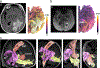

White matter fiber tracking using diffusion magnetic resonance imaging (dMRI) provides a noninvasive approach to map brain connections, but improving anatomical accuracy has been a significant challenge since the birth of tractography methods. Utilizing tractography in brain studies therefore requires understanding of its technical limitations to avoid shortcomings and pitfalls. This review explores tractography limitations and how different white matter pathways pose different challenges to fiber tracking methodologies. We summarize the pros and cons of commonly-used methods, aiming to inform how tractography and its related analysis may lead to questionable results. Extending these experiences, we review the clinical utilization of tractography in patients with brain tumors and traumatic brain injury, starting from tensor-based tractography to more advanced methods. We discuss current limitations and highlight novel approaches in the context of these two conditions to inform future tractography developments.